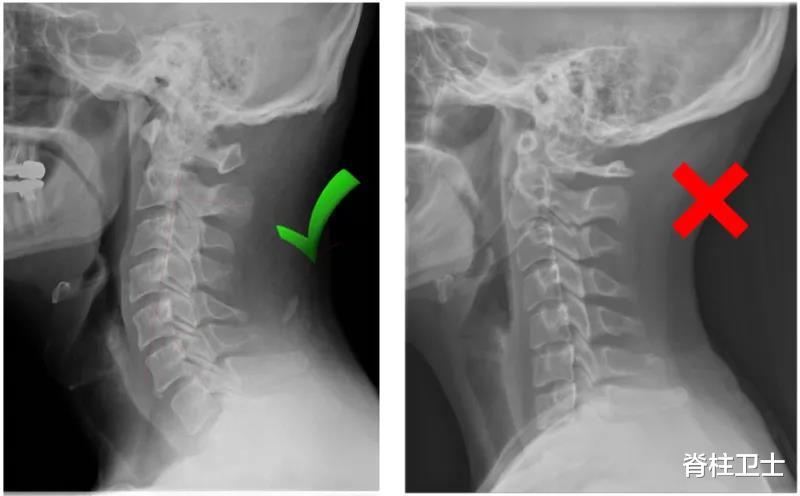

颈椎变直:颈椎的前凸C型弧度减小变直 。

颈椎反弓:颈椎变直后继续发展 , 变成后凸C型 。

02_拍X片

到医院拍个X片 , 能比较直观地看到颈椎曲度的变化 。